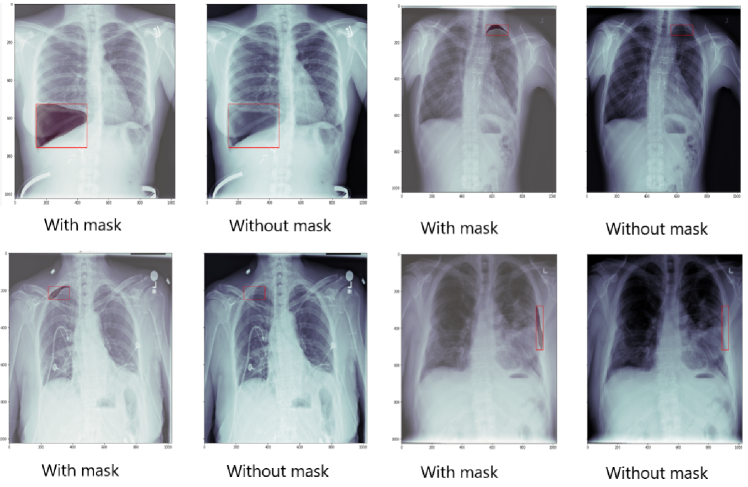

The round-1 training set contains 2,379 positive cases of finding pneumothorax, while the round-2 training set has 2,669 positive cases of finding pneumothorax. Table 2 shows more details for the dataset. RLE masks for the positive cases in the round-1 training set are distributed as follows: 1,755 cases have a single annotation (73.77%) and 624 cases have multiple annotations (26.23%). Whereas in the round- training set, 2,045 cases contain a single annotation (76.62%) and 624 cases contain multiple annotations (23.38%). Figure 5 shows some X-ray images that contain pneumothorax.

Refer to caption

Figure 5: Samples of chest X-ray image containing pneumothorax.

For round-2 of the competition, a new test was released and the training set was updated to include a round-1 test set. We choose the best experiment (Exp5) 2-Stage Training to infer the round-2 test set. This experiment achieves the highest score on both the validation set and the round-1 test set using the TTA technique. Table 7 shows the IoU score for the 2ST-UNet on round-2 validation set with TTA and R-TH configurations. We can see that the use of TTA and R-TH improves the performance of the model for the segmentation task. Figure 8 shows the visual segmentation results of the 2ST-UNet on round-2 validation set.

Figure 8: Visual segmentation results of the 2ST-UNet on the Round-2 validation set.